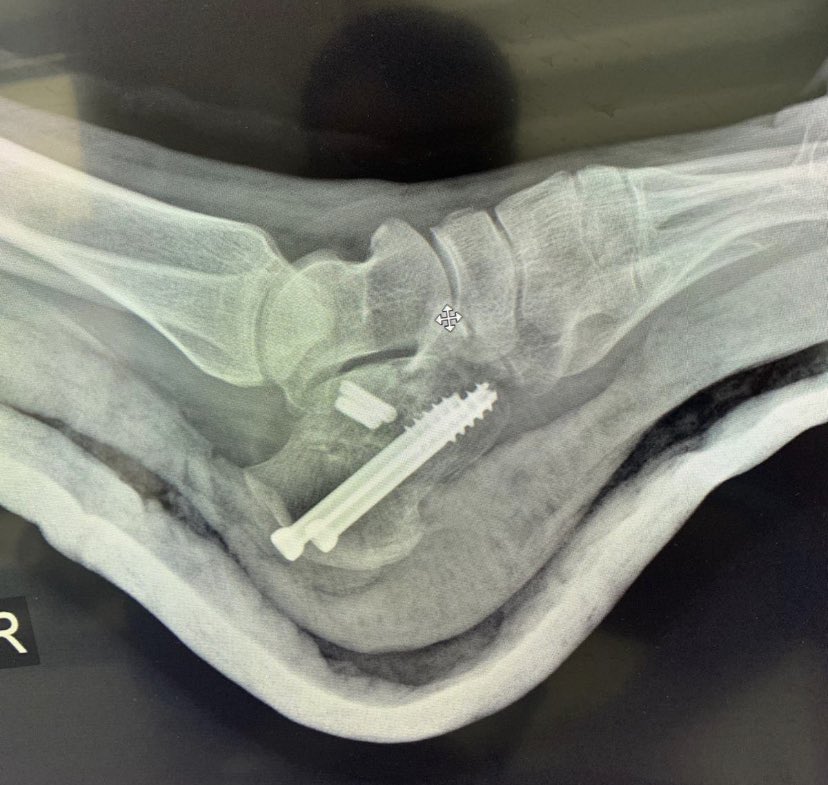

Male 40yo, healthy and physically active.

How do you treat this fracture?

Nonop, ORIF with plate or nailing?

@InvictaOrtho @traumaticum @rkh_md @Gnomelover1970 @aqueipot @DrMarecek

@DrBhavinJadav

#orthotwitter